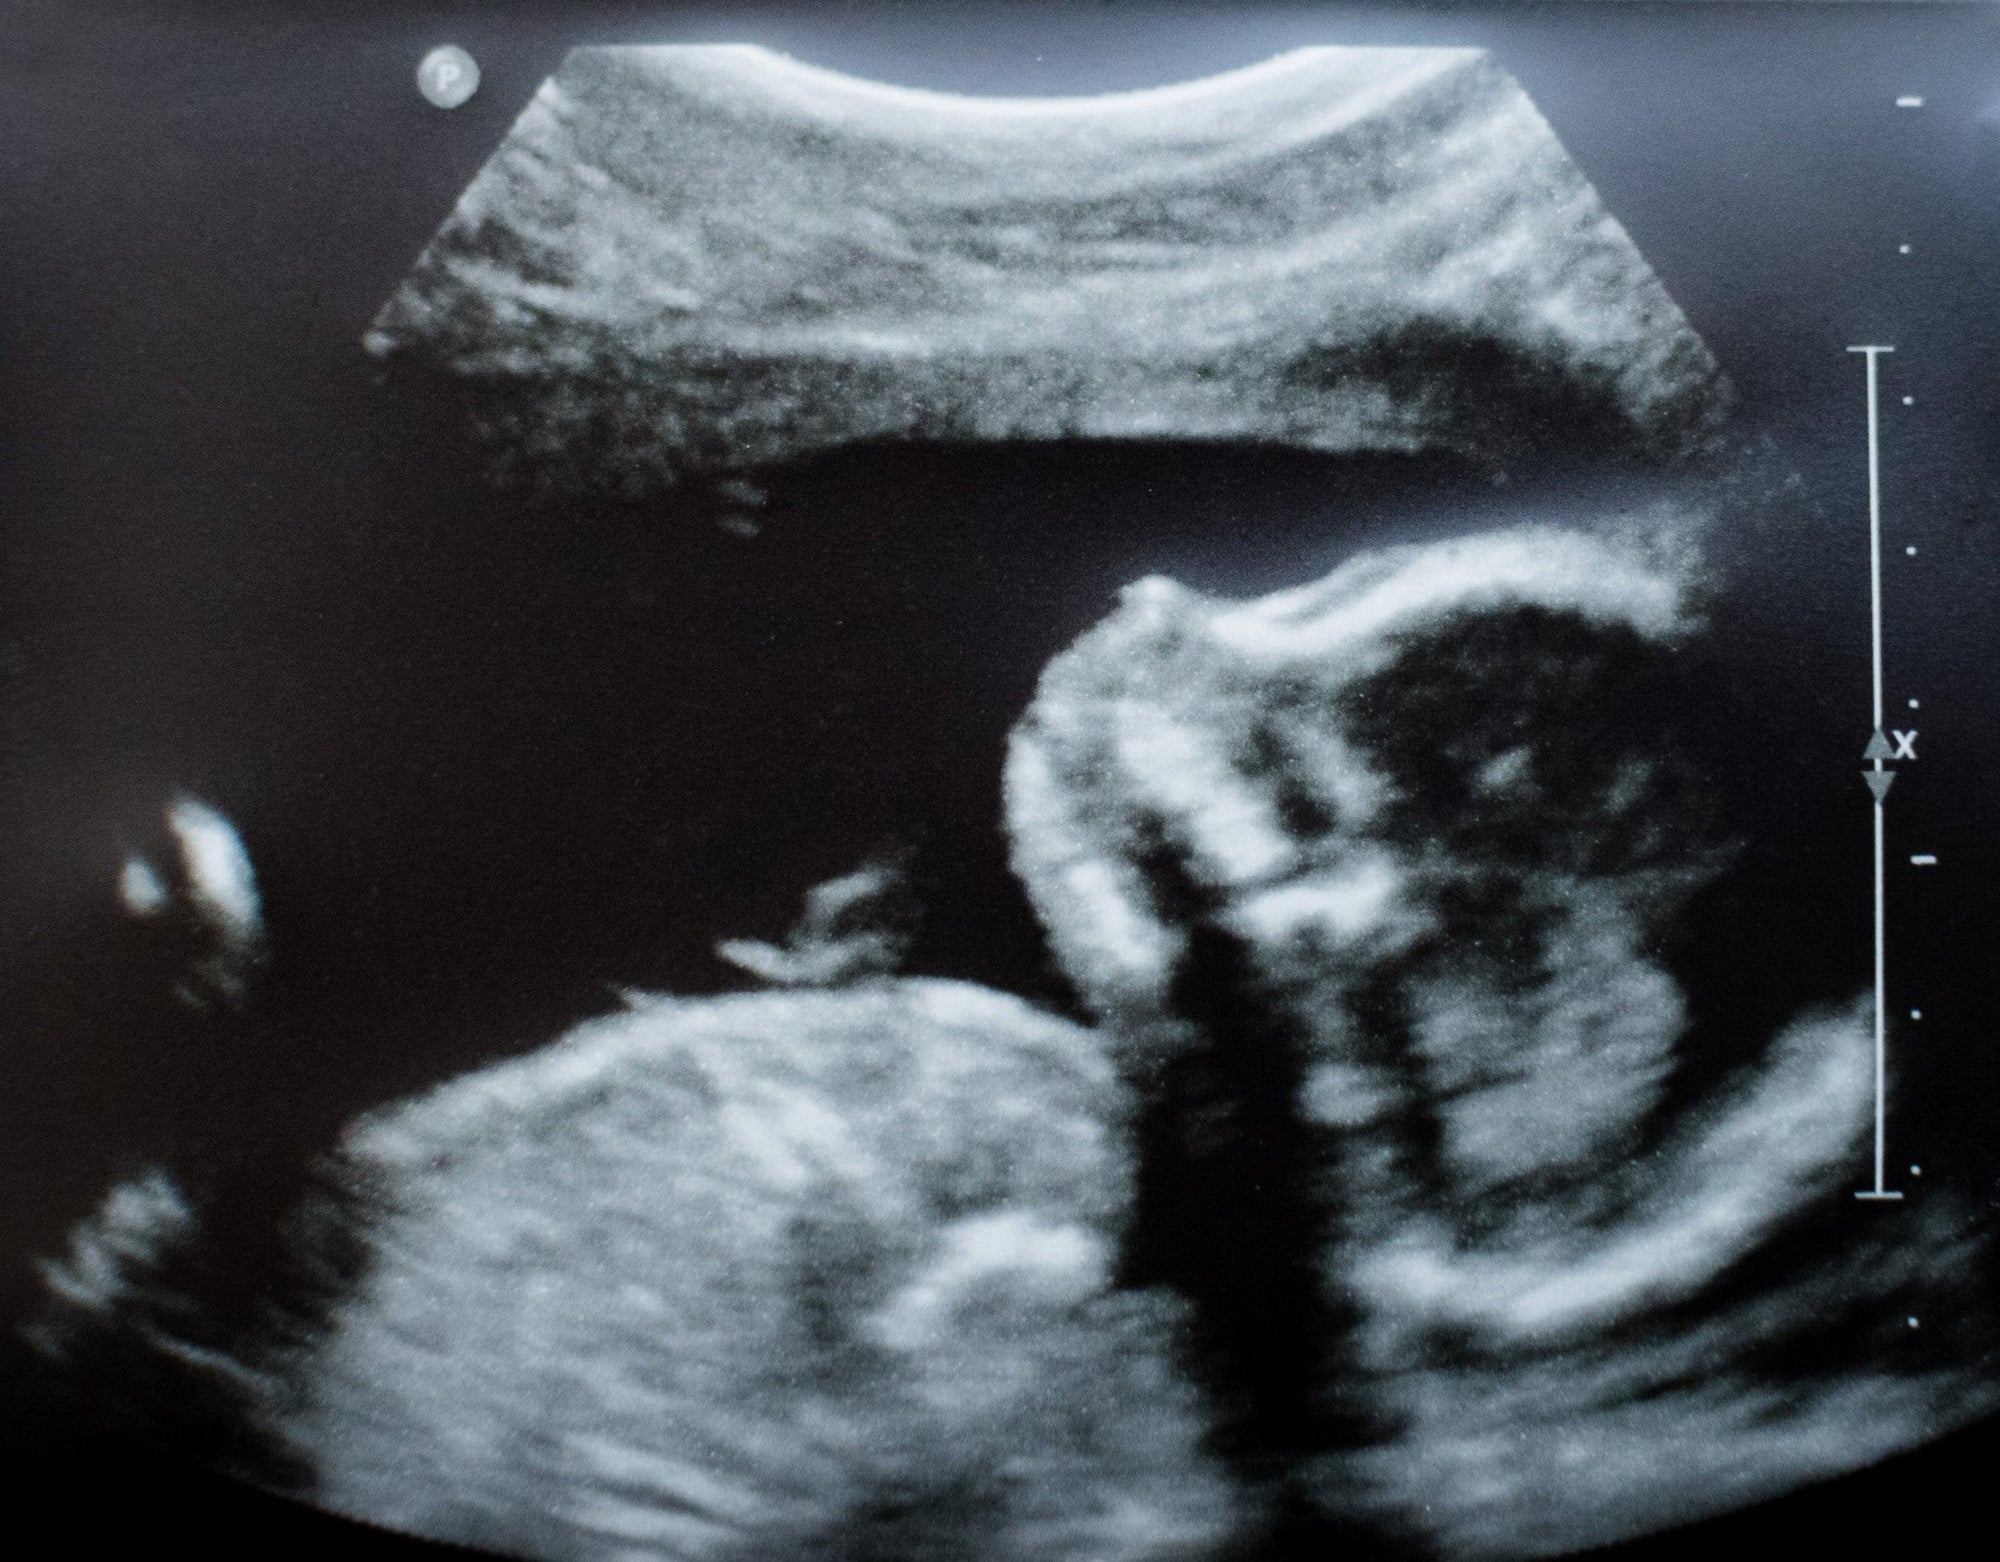

- How doesn't it effect pregnancy?! As I said before, it is common for women to have lower blood sugars throughout the first trimester and sometimes even into the second. In the second trimester and throughout the rest of the pregnancy, most women experience elevated blood sugars as the baby and placenta grow causing insulin resistance from all of those extra hormones. While it sounds scary, hitting the insulin resistance stage is a good sign as it shows the pregnancy is moving along and baby is growing. It just requires frequent monitoring and changes to basal rates and insulin to carb ratios. Because T1D women are considered to be high risk in pregnancy, we get better monitoring and good care! I go to a maternal fetal medicine practice that has a staff of full time CDEs who are always checking on me and taking care of my diabetes concerns. I see the maternal fetal medicine doctor only (no OB) every four weeks for now. Once I am approaching 30 weeks, I will be seen more frequently. T1D pregnant women also get more ultrasounds which is a great thing! You get to see that sweet baby you're carrying more than most other pregnant women.

Throughout the entire pregnancy, it is crucial to have good control of blood sugar levels. It is recommended to have an a1c less than 6, fasting blood sugars between 60-90, and a one hour post prandial blood sugar level lower than 130. I have to admit, these levels intimidated me and still do! However, it is achievable. Not everyday is perfect. I still have good days and bad days but overall everything is going so well. I am healthier than ever and baby boy looks absolutely beautiful.

baby boy at 12 weeks

baby boy at 18.5 weeks